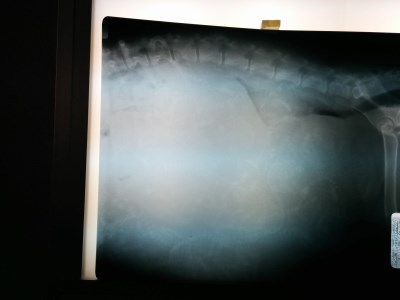

Yes she was LARGE! |